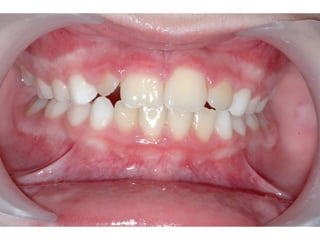

Πρώτη σχολική ηλικία 6-10 ετών

   Αρχίζει αλλαγή των τομέων και η ανατολή των

πρώτων μόνιμων γομφίων (μεικτή οδοντοφυΐα)

   Παρατηρούμε η αλλαγή δοντιών να γίνεται με τη

σωστή σειρά και στη σωστή θέση

   Μπορεί να χρειαστεί πρώιμη ορθοδοντική

θεραπεία, για να αποφευχθούν πιο δύσκολες και

πολύπλοκες εργασίες αργότερα

   Διατήρηση νεογιλών δοντιών στον οδοντικό

φραγμό μέχρι τη φυσιολογική τους απόπτωση